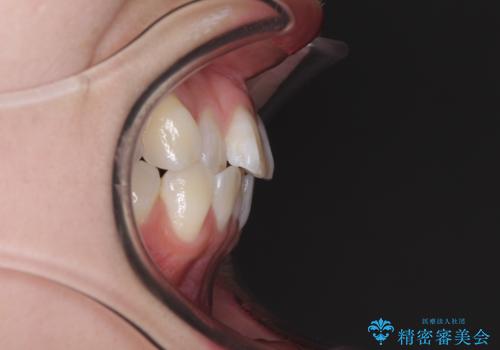

- 海外留学の予定があるが、学生のうちに歯列を整えたいとのことで来院された患者様です。

前歯にデコボコがあり、口元がやや突出した印象があったため、IPR(歯と歯の間を削る)と親知らずを抜歯した上での歯列全体の後方移動をメインに、インビザラインを用いて矯正治療を行うこととしました。

年に一度、夏休みの時期にしか帰国できないため、帰国のタイミングに合わせてマウスピース交換スケジュール治療計画としたため、3年半という期間を要しました。

留学先でもしっかりとマウスピースの装着を実践してくださったので、ご本人の満足のいく仕上がりとなりました。